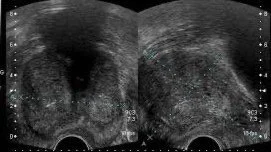

Echographie urologique

Les échographies réalisées en consultation :

échographie vésicale

(pré- et post-mictionnelle)échographie prostatique trans-rectale

échographie rénale morphologique

(pas d’écho-doppler)échographie testiculaire

échographie morphologique de la verge

(pas d’écho-doppler)